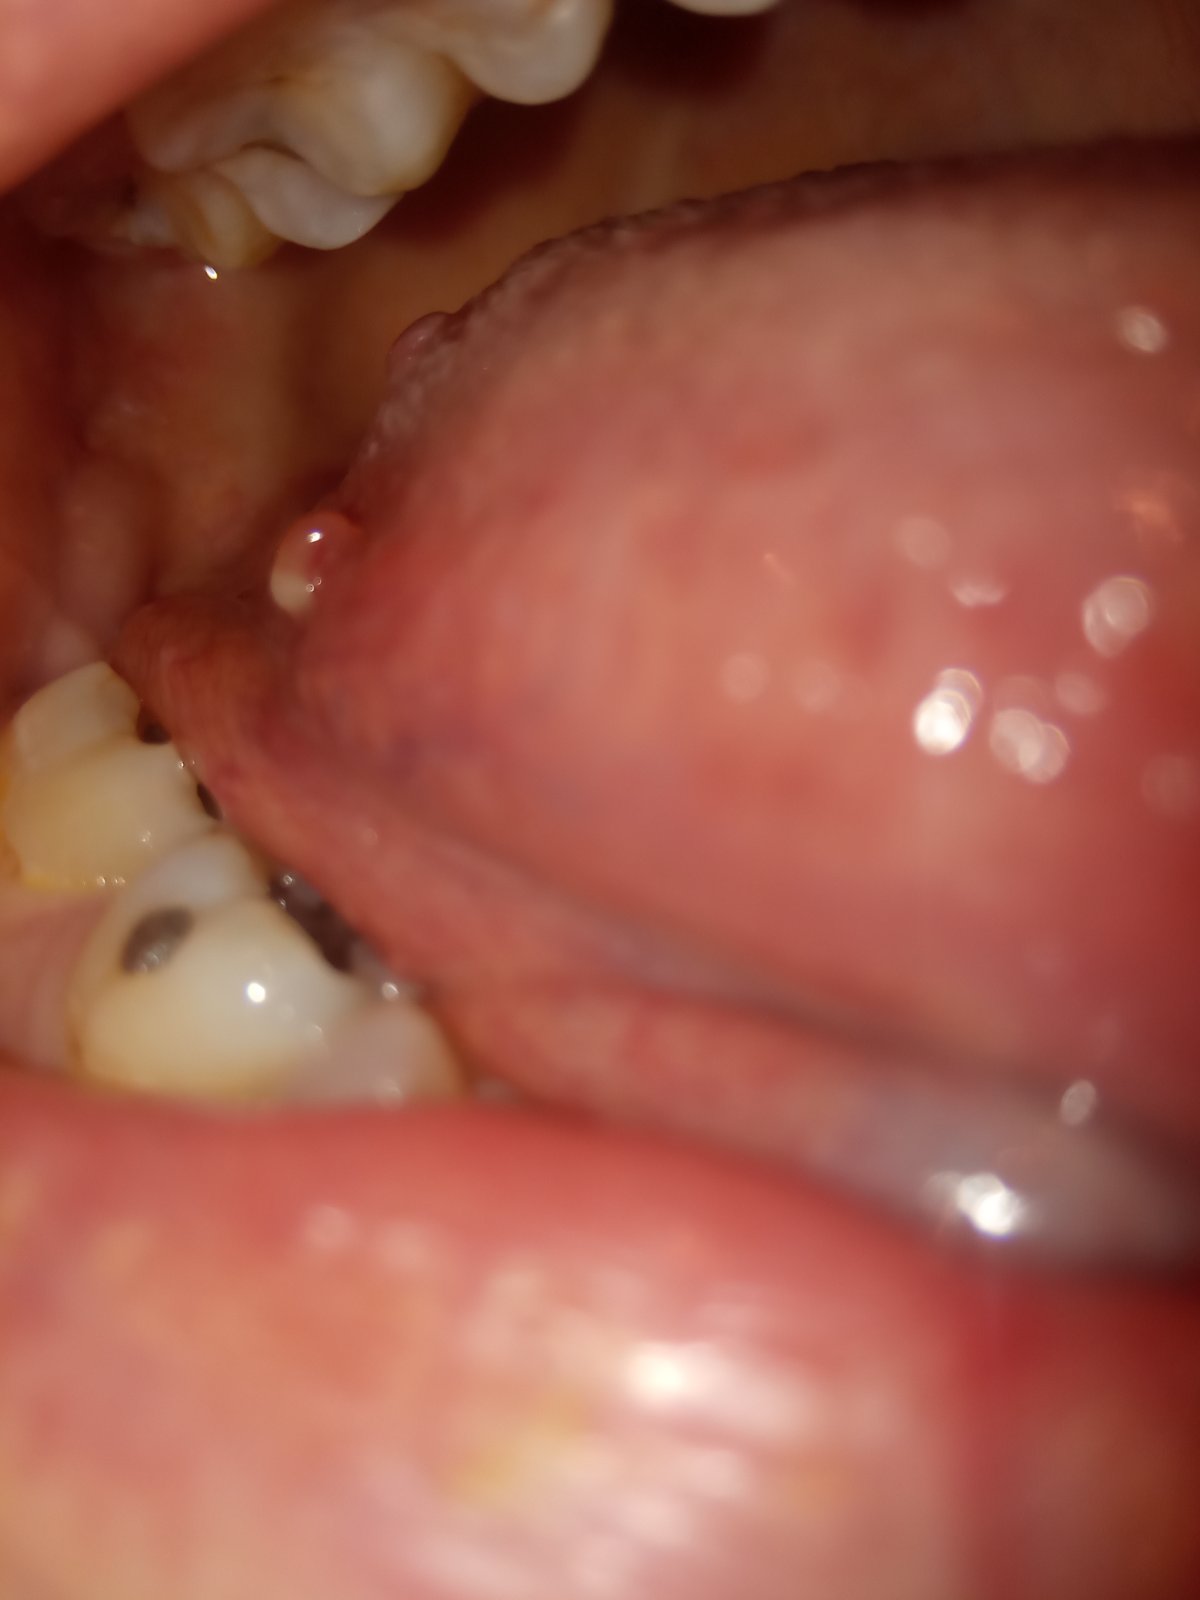

Čo môže byť tá biela guľka vzadu na boku?

Vyzerá ako keby výrastok na jazyku. Mám to tam už asi rok, možno aj viac. Nebolí a ani nerastie. Zubárka povedala, že to zrejme nič nie je.

zrejme pôjde o drobný výrastok.

Ak Vám to vadí alebo zavadzia, tak je vhodné navštíviť ORL lekára, ktorý rozhodne o tom, či sa to má alebo nemá odstrániť.